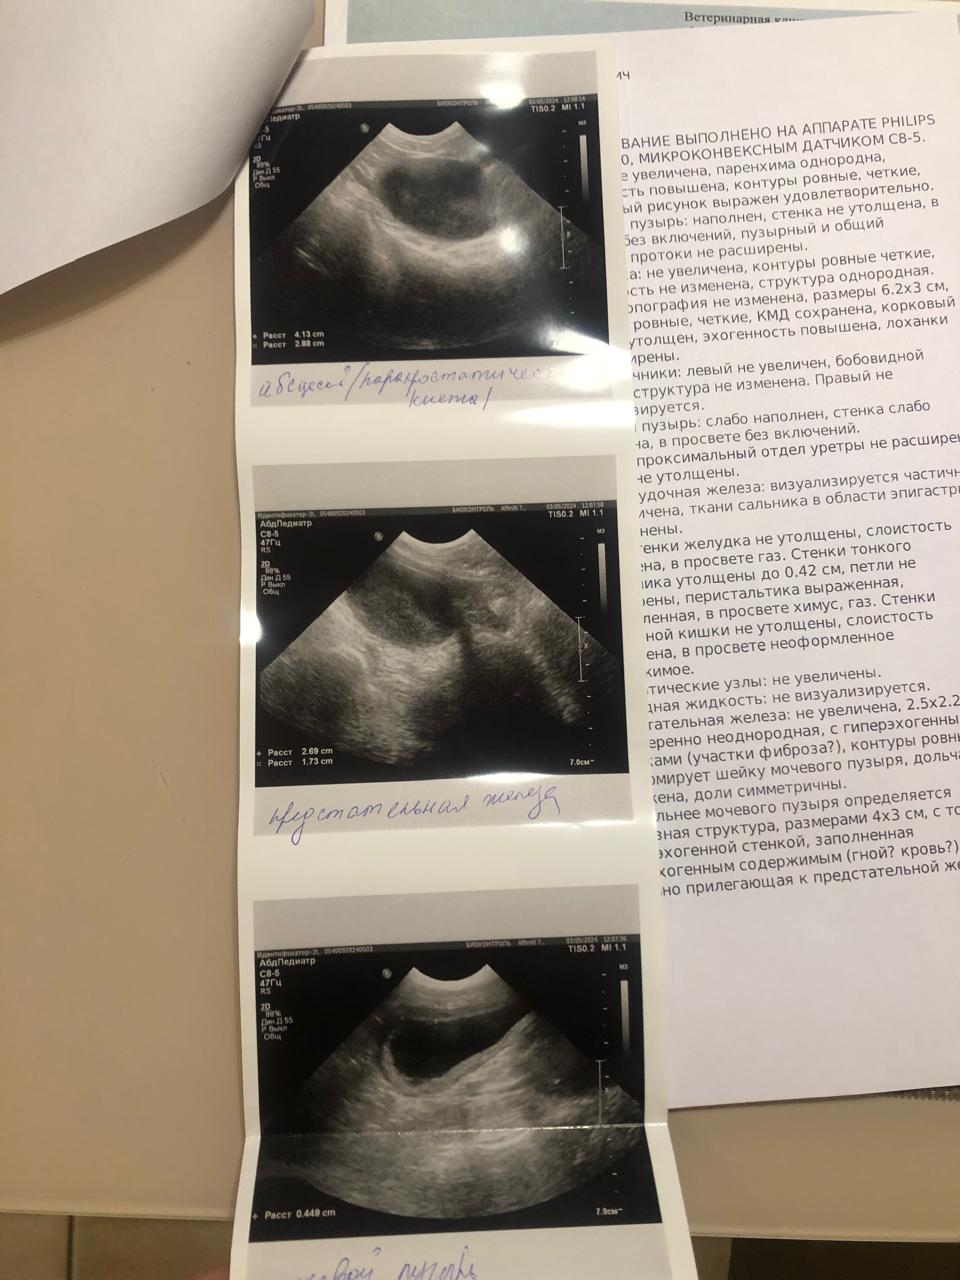

Визит в Био контроль.

IMG-20240503-WA0115.jpg

IMG-20240503-WA0113.jpg

IMG-20240503-WA0111.jpg

IMG-20240503-WA0112.jpg

IMG-20240503-WA0110.jpg

Далее

IMG-20240503-WA0116.jpg

IMG-20240503-WA0114.jpg